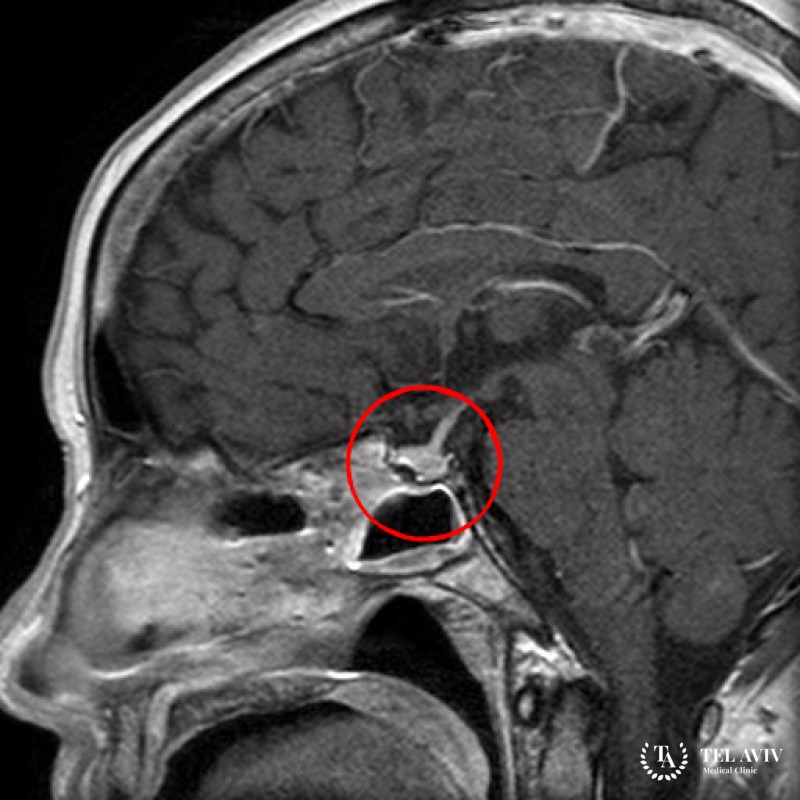

Кортикотропинома – это одна из форм аденомы гипофиза. Доброкачественное, гипофизарное новообразование. Функциональная железистая неоплазия встречается в пятнадцати процентах среди опухолей в головном мозге. Место дислокации доброкачественной патологии – питуитарная железа. Кортикотропиному относят не к опухолям в мозге. Ее классифицируют в качестве эндокринного новообразования.